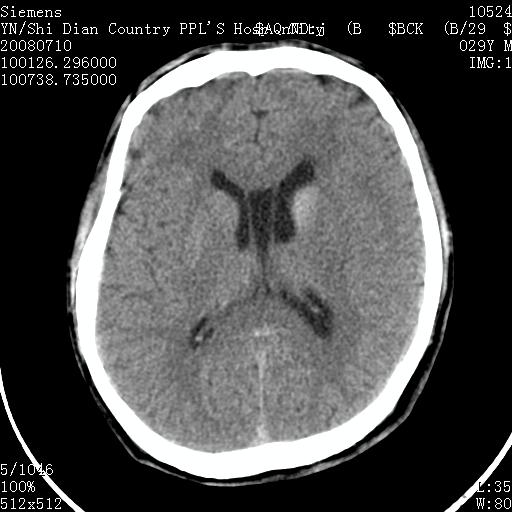

以下是引用随光逐影在2008-7-10 15:19:00的发言:[br]1)考虑左侧尾状核钙化。2)透间隔间腔与vergae腔并存。

以下是引用dyqct在2008-7-10 15:30:00的发言:[br][quote]以下是引用随光逐影在2008-7-10 15:19:00的发言:[br]1)考虑左侧尾状核钙化。2)透间隔间腔与vergae腔并存。

以下是引用卜一在2008-7-10 16:43:00的发言:[br]1)考虑左侧尾状核钙化。2)透间隔间腔形成。支持!